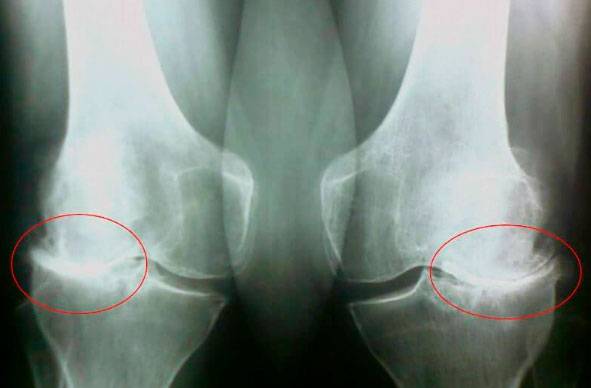

Ба ин суратхо нигаред, мебинед, ки дар расми рост ягон фосилаи бугум вучуд надорад, устухонхо ба хам мемоланд ва боиси дарди сахт мегарданд. Ва боздоштани ин раванд хеле душвор аст! Пас аз чанд сол одам маъюб мешавад ва худро таъмин карда наметавонад.

Доктори илмҳои тиб Владимир Бенеш Пеш аз ҳама, ин осеб ва бори вазнин аст. Вазни зиёдатӣ инчунин ба буғумҳои шумо фишори бештар меорад. Камҳаракатӣ, стресс, миқдори намак ва шакар дар ғизо - ҳамаи ин бофтаи пайҳоро нарм мекунад, онро фарсуда мекунад ва борик мекунад. Бо ҳар як ҳаракати нав пойҳо коста шуда, деформатсия мешавад, устухонҳо ба ҳамдигар мекӯбанд, ки боиси дарди шадид мегардад .